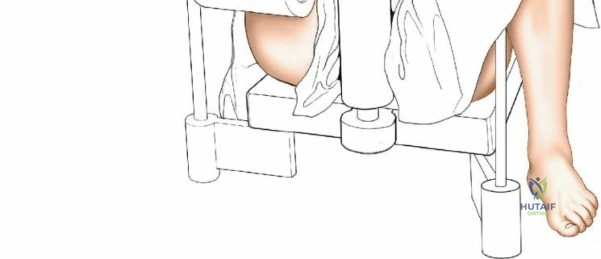

Supine on a Traction Table:

- Setup: The patient is placed supine on a radiolucent operating table. The affected hip is flexed to approximately 60 degrees. A support is strategically placed behind the posterior aspect of the distal thigh to allow the knee to flex freely. Crucially, care must be taken to position this support well away from the popliteal fossa to avoid compression of the popliteal artery and vein, which can lead to neurovascular compromise or compartment syndrome. The knee is then flexed to 100 to 120 degrees. Traction is applied by strapping the patient's foot to the sole plate of the traction apparatus.

- Advantages:

- Provides superior control over fracture reduction, particularly for comminuted or highly unstable patterns, allowing for precise length and alignment restoration.

- Facilitates easier distal locking as the limb is rigidly held.

- Frees up surgical assistants, who are not required to hold the leg.

- Disadvantages:

- Potential for pressure injuries in the popliteal fossa if support is misplaced.

- Risk of compartment syndrome due to prolonged traction.

- Can restrict access to the proximal tibia for very high entry points if knee flexion is insufficient.